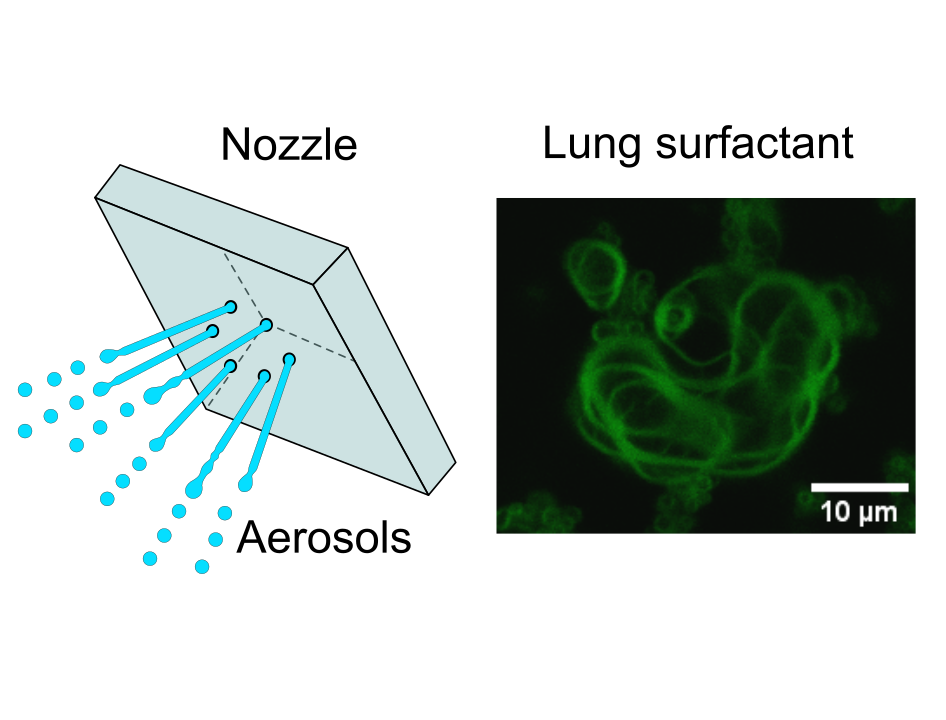

Aerosol drug delivery

High shear forces in nebulization is detrimental to complex surfactants, i.e. lung surfactant. Here, we report a new nebulization technique with low shear energy input to preserve the structural integrity of lung surfactant.